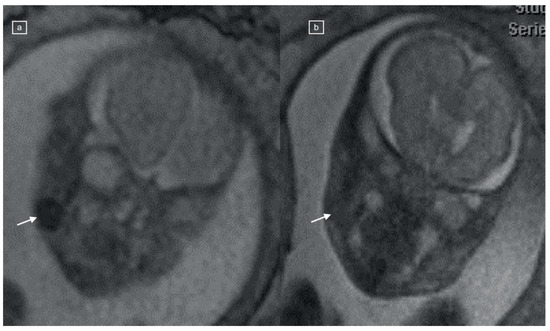

Figure 1.

(a) Axial, (b) coronal, and (c) sagittal TRUFI MR images of a 21-week fetus, demonstrating bilateral, oval low-signal-intensity buccal fat pads (black arrows), corresponding to (d) T1 VIBE hyperintensity.